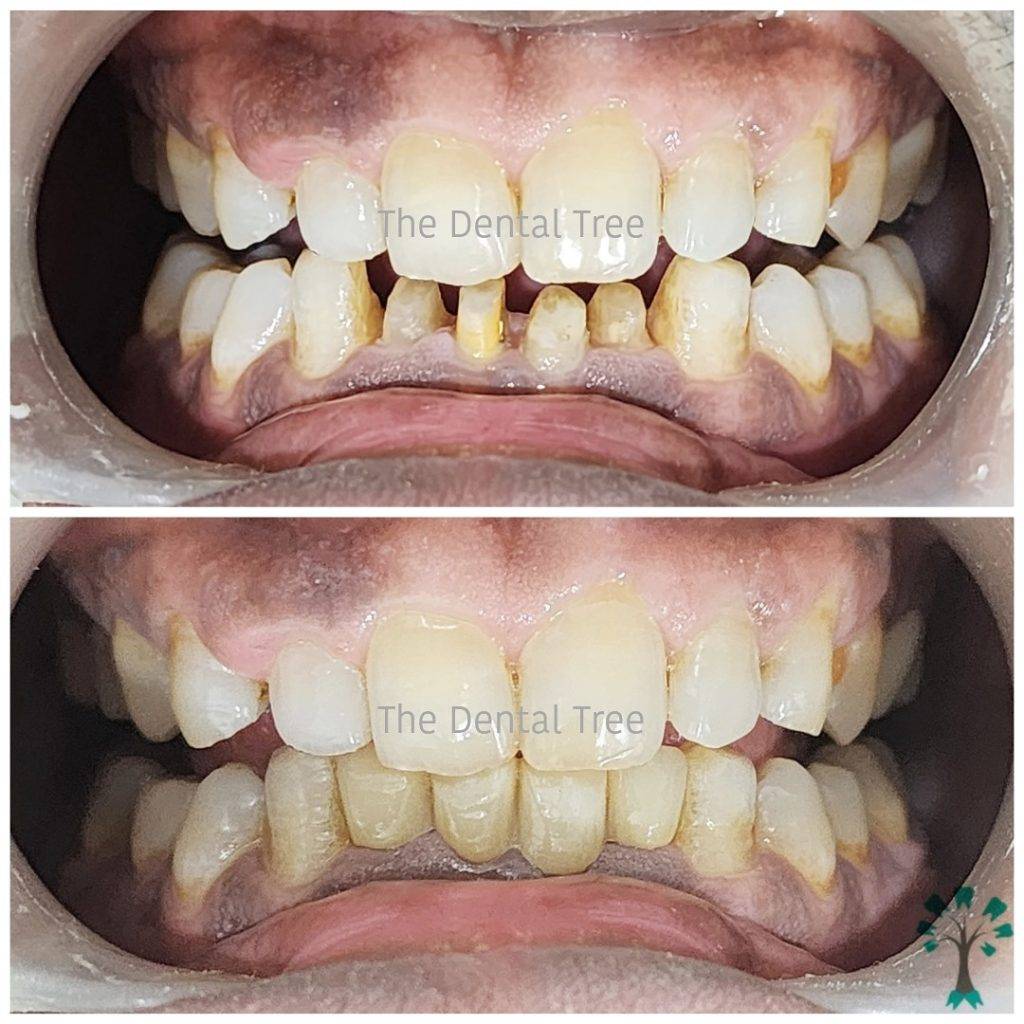

Treatment Gallery

At The Dental Tree & Facial Cosmetic Centre, the centre of our universe is our patients. Satisfaction of our patients has always been our top priority and always will be. This is the reason why we are the Best Dental Clinic in Indirapuram and why we do what we do.

- Dentists also offer cosmetic procedures such as teeth whitening, veneers, and dental implants to improve the appearance of the smile.

Our Gallery